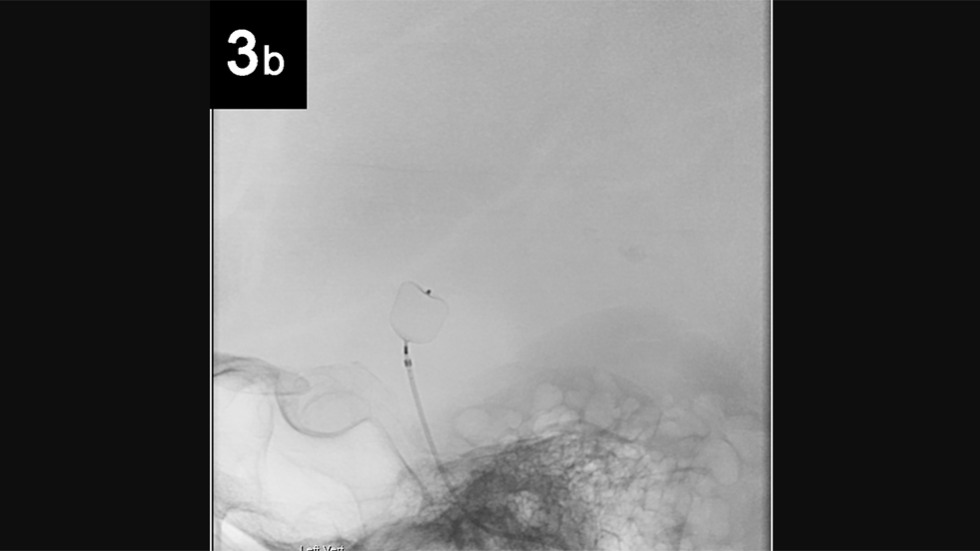

Balloon-Assisted Coiling

Balloon Assisted Coiling: Balloon-assisted coiling is used to treat wide-necked (opening too large to keep the coil in place), complex-shaped cerebral aneurysms.